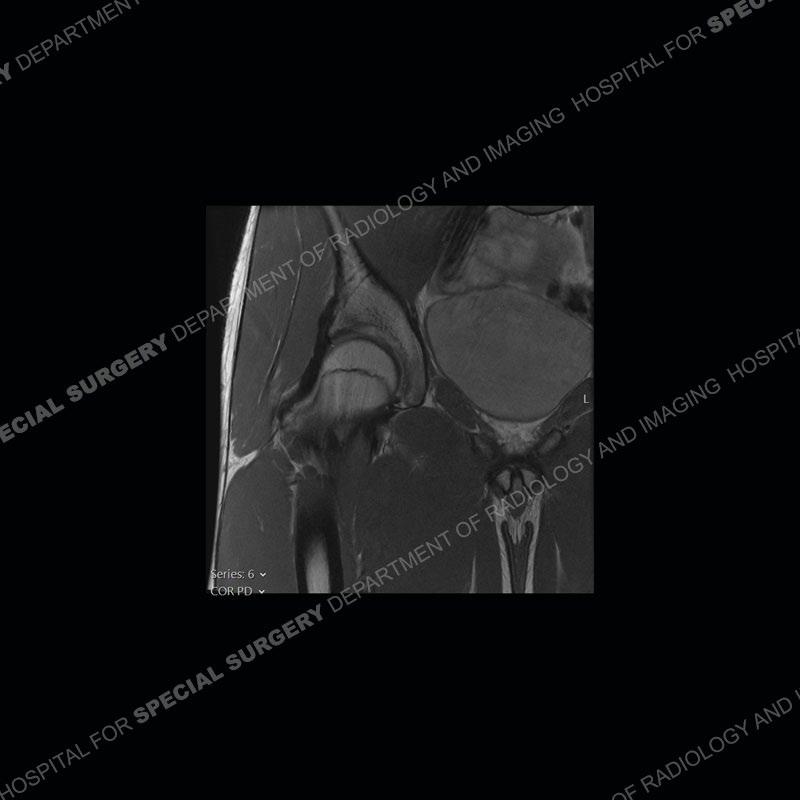

The radiographs demonstrate a suggested bony protuberance or excrescence emanating from the superior aspect of the acetabulum. On the MRI, seen is a large amount of bone about the anterior inferior iliac spine (AIIS) at the level of the origin of the direct head of the rectus femoris. This bone pedunculates inferior to the acetabular rim. No edema pattern is present on the IR sequence and the contralateral left hip acts as a nice internal control where the bony prominence is not present.

The anterior inferior iliac spine is the attachment site of the direct head of the rectus femoris. With avulsion, hematoma and heterotopic ossification may form or in some situations, chronic overuse may precipitate a large enthesophyte. Whatever, the etiology, if bone is present about the AIIS with flexion and internal rotation about the hip, impingement may be precipitated between the bone and the proximal femur. This leads to pain and a limited range of motion.

Prior classification of the ASIS has been performed by Kelly et al. A type I has a smooth wall between the AIIS and the acetabular rim, a type II is when the AIIS extends to the level of the acetabular rim, and a type III is when the AIIS extends distally to the rim. Multiple studies have shown that a type II or type III may be associated with impingement. It is important to always remember that the imaging can only demonstrate findings that may be seen in impingement, but the actual impingement remains a clinical diagnosis.